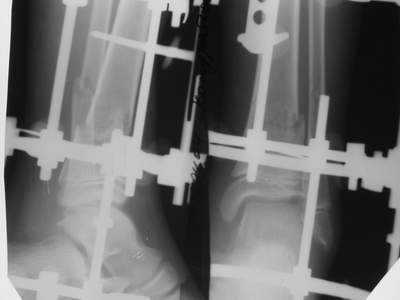

Вытяжение